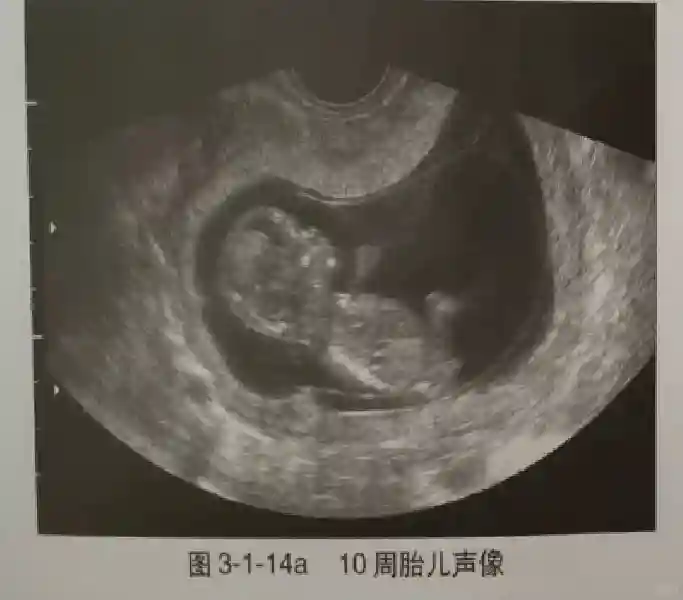

早孕早期建议采用阴道超声检查,以便早期了解胚胎发育情况,发现异常妊娠。早孕期超声是指从证实宫内妊娠到妊娠13+6周期间超声观察妊娠的情况,10周以前为胚胎,10周后为胎儿。

3️⃣胚胎:胚胎通常在6-7周时可以为超声显示,起初为胎芽,表现为卵黄囊一侧局部组织增厚,达到1 -2 mm 时才有可能为超声测量出来。达4-5mm时可见胎心搏动,相应孕周为6-6.5周,妊娠囊大小为13-18mm。胚芽长度≥7㎜时仍未见心管搏动,提示胚胎停止发育。胚胎的出现和妊娠囊直径的关系:妊娠囊直径> 16 mm 时,经阴道超声应显示胚胎。妊娠囊直径> 25 mm 时,经腹超声均应显示胚胎。